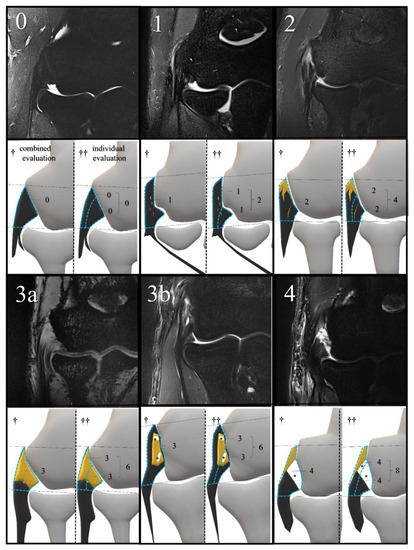

2.3. MRI Scoring and Evaluation